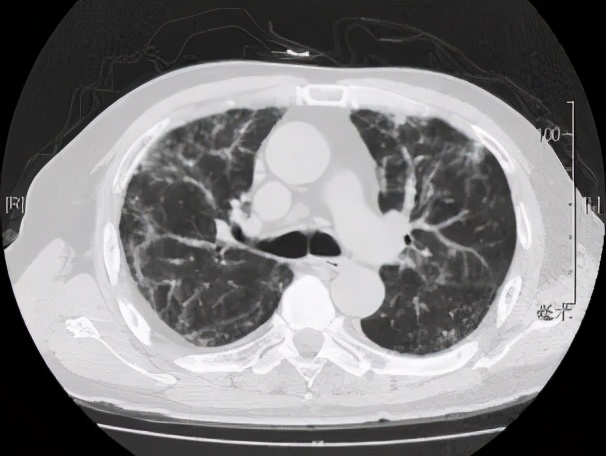

本院胸部CT(2019-08-30)示: 双肺弥漫性间质性改变,有网格状改变、毛玻璃影、局部有支气管牵拉形成支气管扩张的表现。

动脉血气(09-02):PaO2:68mmHg,PaCO2:35mmHg。动脉血气(09-11):PaO2:65mmHg,PaCO2:37mmHg。胸CT和肺功能都指向肺弥漫性间质性病变。

追溯患者2018年体检胸部CT(2018-1-22) :两肺下叶轻度间质增生,无显著双肺弥漫性间质改变。而且近一个月出现气促症状、低氧血症,说明间质性病变有活动性。